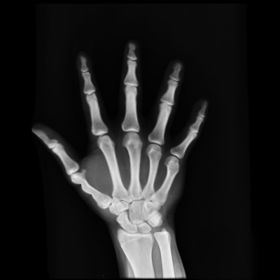

We then consider another example of registering two hand X-ray images with larger deformations (see Fig. 8(a) for the source image, Fig. 8(b) for the target image, and Fig. 8(c) for their absolute intensity difference). The warped image produced by our proposed method (Fig. 8(d)) again closely resembles the target image with the intensity difference significantly reduced (see Fig. 8(e)). Fig. 8(f) shows that the mapping is smooth and bijective. For comparison, note that LDDMM [5] fails to match the fingers (Fig. 8(g)). While DROP [18] is capable of registering the fingers (Fig. 8(h)), it distorts the boundary shape of the overall image (Fig. 8(i)).